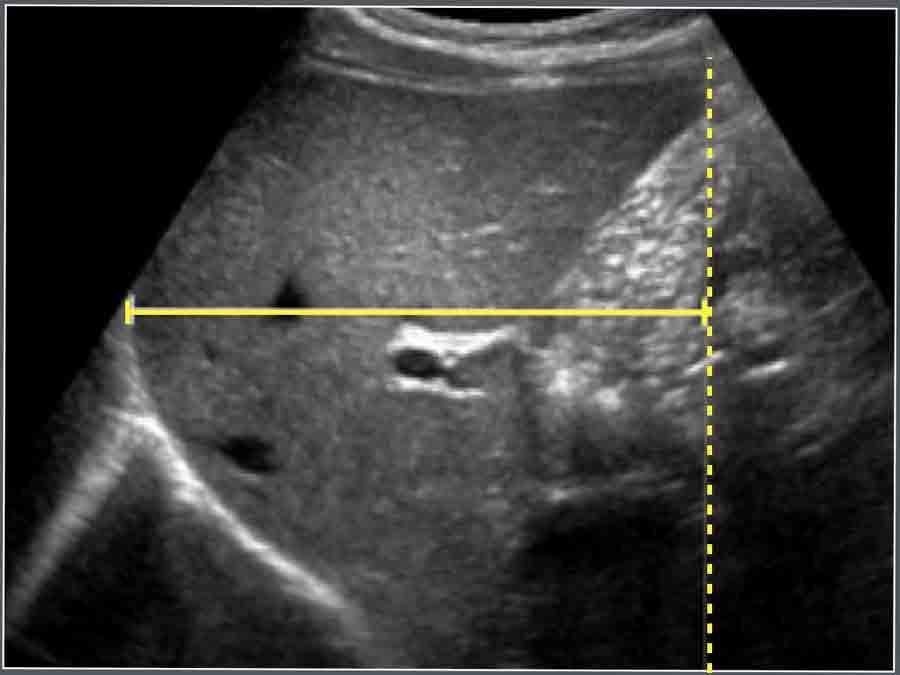

Ống Mật Chủ

Vật liệu và Phương pháp

Tổng cộng 173 bệnh nhi liên tiếp (100 bé trai và 73 bé gái) được chỉ định siêu âm bụng vì lý do không liên quan đến bệnh lý gan mật đã được đưa vào nghiên cứu. Độ tuổi dao động từ 1 ngày đến 13 tuổi (trung vị 5,0 tuổi).

Ở tất cả các đối tượng, đường kính ống mật chủ đo được ≤ 3,3 mm.

Hình ảnh

Hình ảnh siêu âm cắt ngang ống mật chủ và các cấu trúc giải phẫu xung quanh.